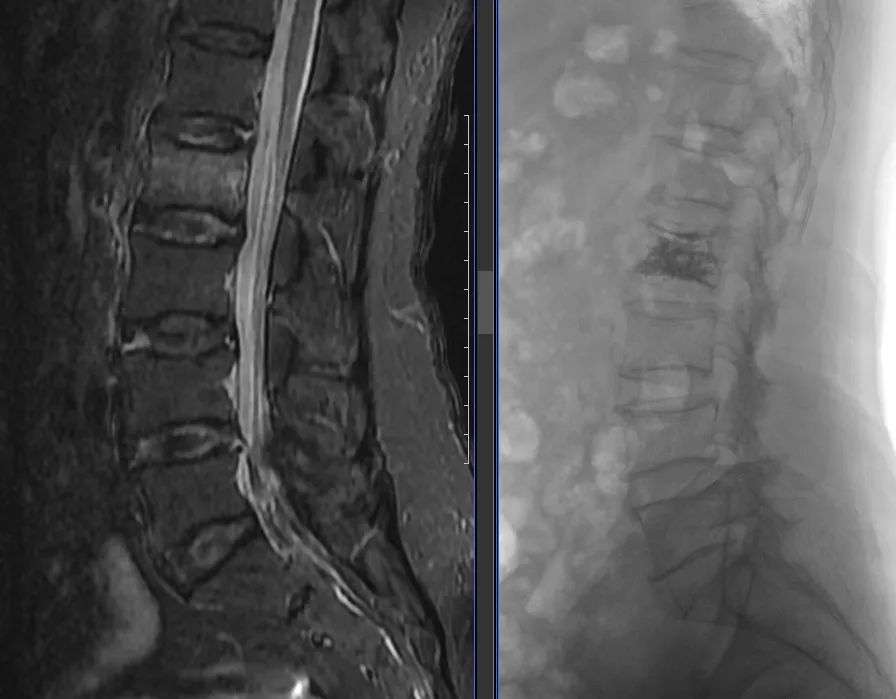

两位老人:白某(94岁,ID:752351)和戴某(93岁,ID:712140),都是因低能量损伤导致胸腰椎骨质疏松性椎体压缩性骨折,受伤后老人因疼痛导致活动严重受限,生活质量下降。由于患者高龄且均患有多种慢性心脑血管及内分泌疾病,快速手术并恢复正常生活迫在眉睫。在家属的充分信任下,骨脊柱科医生为他们实施了胸腰椎骨折椎体后凸成形术,手术效果立竿见影,患者和家属非常满意。

呼和浩特市第一医院骨脊柱科在胡继平主任的带领下,科室医生规范化、标准化开展椎体强化手术(PKP或PVP),每年采用该术式治疗骨质疏松性脊柱椎体压缩骨折近百例。高龄患者已经不再被视为手术的绝对禁忌,在快速康复(ERAS)理念的指导下,可使患者在入院后24小时内完成术前检查,术后次日佩戴支具下地活动,住院日3~5天,取得了良好的手术效果,助力患者尽快恢复正常生活。